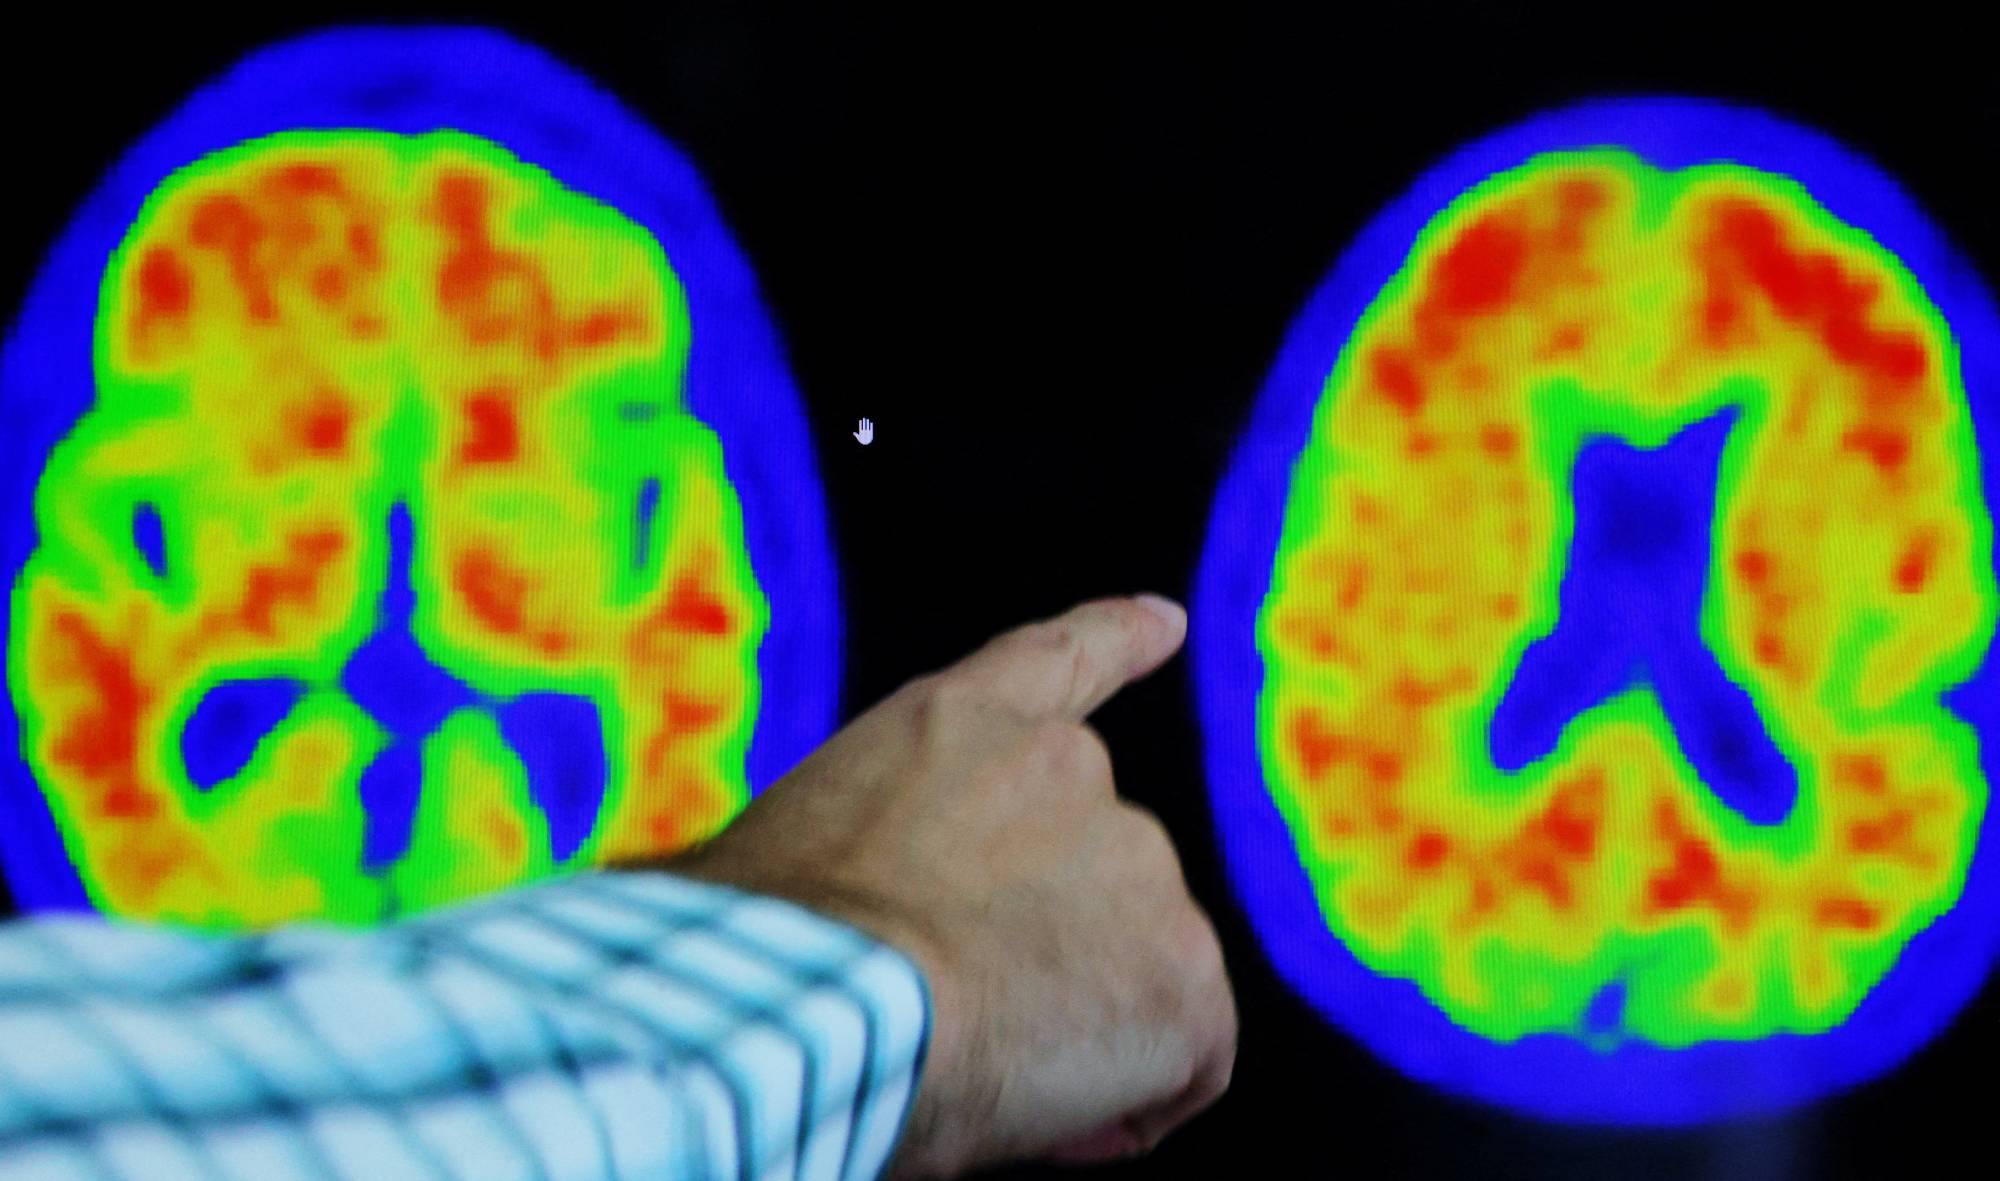

Alzheimer's disease experts are revamping the way doctors diagnose patients with the progressive brain disorder — the most common type of dementia — by devising a seven-point rating scale based on cognitive and biological changes in the patient.

The proposed guidelines, unveiled by experts on Sunday in a report issued at an Alzheimer's Association conference in Amsterdam, embrace a numerical staging system assessing disease progression similar to the one used in cancer diagnoses. They also eliminate the use of terms like mild, moderate and severe.

The revamp — replacing guidelines issued in 2018 — was prompted by the increased availability of tests detecting key Alzheimer's-related proteins such as beta amyloid in the blood and new treatments that require confirmation of disease pathology prior to use.